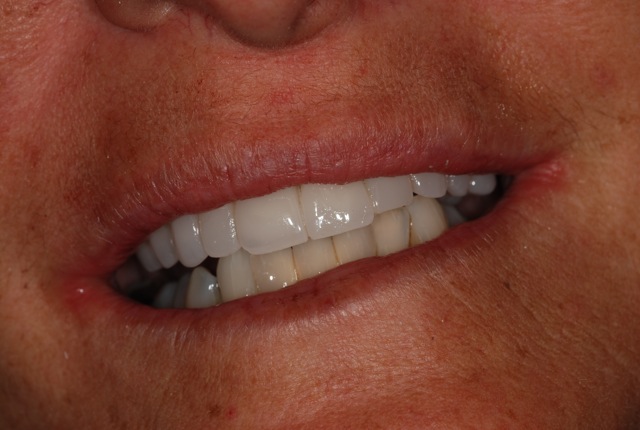

Il caso clinico che presentiamo si tratta di paziente sesso F anni 54, si presenta alla nostra osservazione mandata da altro collega, paziente con elementi dentali irrecuperabili dal punto di vista parodontale a livello dell’arcata superiore. Già eseguito visite in altro studio, il protocollo che era stato prospettato consisteva nell’avulsione di tutti gli elementi dentari dell’arcata superiore, un periodo di guarigione di circa quattro mesi, in questo periodo avrebbe dovuto portare una protesi amovibile con palato, dopo di che, inserimento di quattro impianti, ad avvenuta osteointegrazione circa cinque mesi successiva solidarizzazione con barra e protesi ancorata da attacchi. Abbiamo spiegato alla paziente che il protocollo era decisamente corretto,riabilitazioni di questo tipo hanno un follow up di molti anni. La paziente non voleva decisamente portare una protesi mobile. Abbiamo spiegato alla paziente che vi era anche un'altra possibilità, si trattava del carico immediato, la paziente molto motivata si era ripromessa di seguire tutte le indicazioni del caso. Non essendo possibile evitare contatti occlusali quando si riabilita un’intera arcata, il paziente deve essere istruito e utilizzare la protesi provvisoria fissa con moltissima attenzione, quindi la dieta per almeno due mesi deve essere morbida e liquida. Dopo attenta valutazione radiografica e tomografica, confezionamento di protesi armata in resina, si programma l’intervento.(foto 1,2,3,4,5,6,7,8,9) Avulsioni dentarie, incisione e scollamento del lembo, sottopreparazioni dei siti a 3,25 per inserire impianti Pitt Easy superficie purotex di diametro 3,75, tutti gli impianti vengono serrati a 40N.(foto 10,11) Vengono adattati abutment all’esterno del cavo orale, posizionati e serrati manualmente, ribasato provvisorio,rifinito e posizionato. La paziente viene dimessa con le terapie del caso.(12,13,14,15,16,17,18,19) L’intervento è iniziato alle 10,00 del mattino terminato alle ore 15,00 del pomeriggio. Molto importante in interventi di questo tipo è l’utilizzo di suture assorbibili in quanto il provvisorio non verrà rimosso prima di tre mesi. Il monitoraggio di tali pazienti deve essere continuo. (foto 20 otto giorni dall’intervento) A distanza di sei mesi altri due impianti sono stati inseriti in posizione 2,3 e 2,5. Sedi che in primo intervento si presentavano deficitarie, ma dopo rigenerazione ossea si è potuto intervenire. A distanza di altri sei mesi è stato applicata la protesi fissa in zirconio ceramica, il carico di questo lavoro ha un follow up di due anni. (foto 21,22,23) Da una attenta analisi della letteratura sul carico immediato di impianti endossei orali nell’uomo, si possono trarre alcune considerazioni. Possiamo notare per esempio che le prime sperimentazioni cliniche sul carico immediato sono state effettuate con overdenture mandibolari; queste, basandosi su un elevato numero di casi presi in considerazione (quasi 4000 impianti complessivamente inseriti in circa 1000 pazienti), hanno dimostrato una eccellente percentuale di successo a lungo termine. Successivamente il protocollo a carico immediato è stato utilizzato anche per le arcate complete fisse, soprattutto a livello mandibolare, raggiungendo percentuali di successo almeno pari se non addirittura superiori alle overdenture, considerando follow up fino a 10 anni. Invece per le riabilitazioni totali a livello dell’arcata superiore e altri tipi di costruzione protesica quali corone singole e protesi fisse monolaterali, sebbene i dati sinora disponibili forniscano risultati assai incoraggianti, è consigliabile attendere ulteriori evidenze scientifiche che dimostrino la reale predicibilità a lungo termine. Si può concludere che le riabilitazioni tipo over-denture e le arcate complete fisse a livello mandibolare rimangono a tutt’oggi le indicazioni più predicibili secondo i dati della letteratura e gli studi clinici condotti.